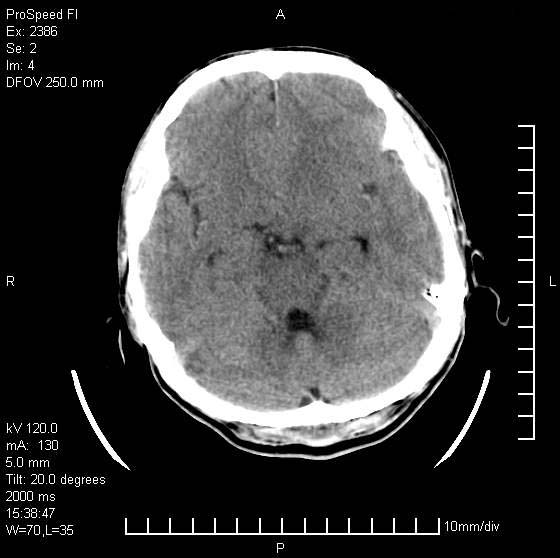

以下是引用天南地北在2007-9-19 18:43:00的发言:[br]典型慢性硬膜外血肿[br][br][本贴已被 天南地北 于 2007-9-19 18:44:11 修改过]

以下是引用曼一拍在2007-9-20 11:06:00的发言:[br]支持慢性硬膜下血肿.[br]慢性硬膜下积液:血肿有包膜,ct值稍高于脑脊液,增强可有染色。不典型者血肿可多呈梭形.是硬脑膜与蛛网膜之间的潜在腔隙内的血肿。[br]鉴别:[br]1\\硬膜外血肿:是颅脑外伤后脑膜或板障内血管破裂,血液在颅骨与硬膜之间积聚所致.通常是脑膜动脉破裂,也可因静脉窦破裂或颅骨的板障静脉出血,发生于外伤的着力部,常与颅骨骨折并存。脑膜动脉出血则急,若是板障静脉出血在则可有慢性。[br]2\\硬膜下积液:(硬膜下水瘤)[br]是由于蛛网膜破裂,脑脊液经蛛网膜破口进入硬膜下腔不能回流。或水肿阻塞而形成。[br]ct表现:颅骨内板下方新月形低密度区近似脑脊液密度;占位效应清,周围无脑水肿。[br]